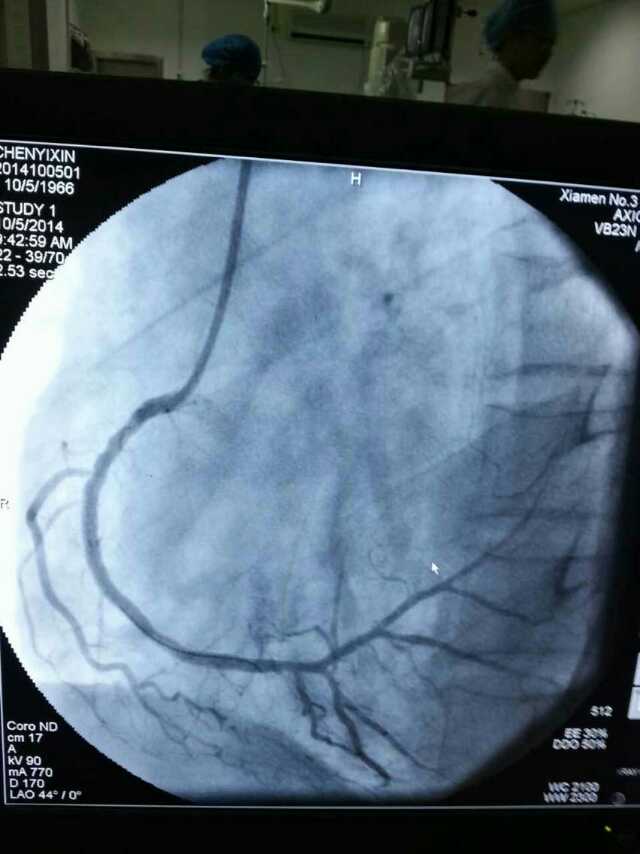

3月20日,家住翔安的庄先生为感谢跳蛋视频 心血管内科的医护人员在第一时间对他的病情给予明确诊断,并及时采取有效治疗措施,让他的心脏病很快得到康复回家。特地送来一面写着“德医双馨,妙手回春”锦旗以表达他们满满的感激之情。